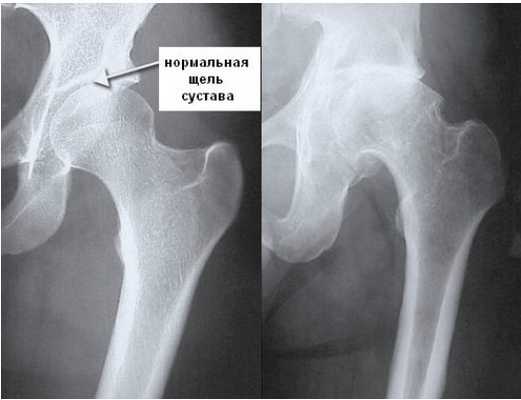

Снимок 1. На этом рентгеновском снимке изображен здоровый тазобедренный сустав. Мы можем здесь увидеть:

- правильную округлую форму головки бедренной кости;

- нормальных размеров суставную щель, т. е. достаточное расстояние между головкой бедренной кости и сочленяющейся с ней вертлужной впадиной.

Здоровый тазобедренный сустав. Фотография из архива доктора Евдокименко

Тем не менее этому пациенту почему-то поставили диагноз «коксартроз второй стадии» и приговорили к операции по замене сустава.

На самом деле никакого коксартроза у пациента не было и в помине. Да, он жаловался на боли в бедре, но эти боли были вызваны грыжей межпозвоночного диска и защемлением бедренного нерва (что впоследствии подтвердила томограмма позвоночника). Соответственно, операция по замене сустава пациенту была не нужна, а боли в бедре прошли после успешного лечения грыжи диска.